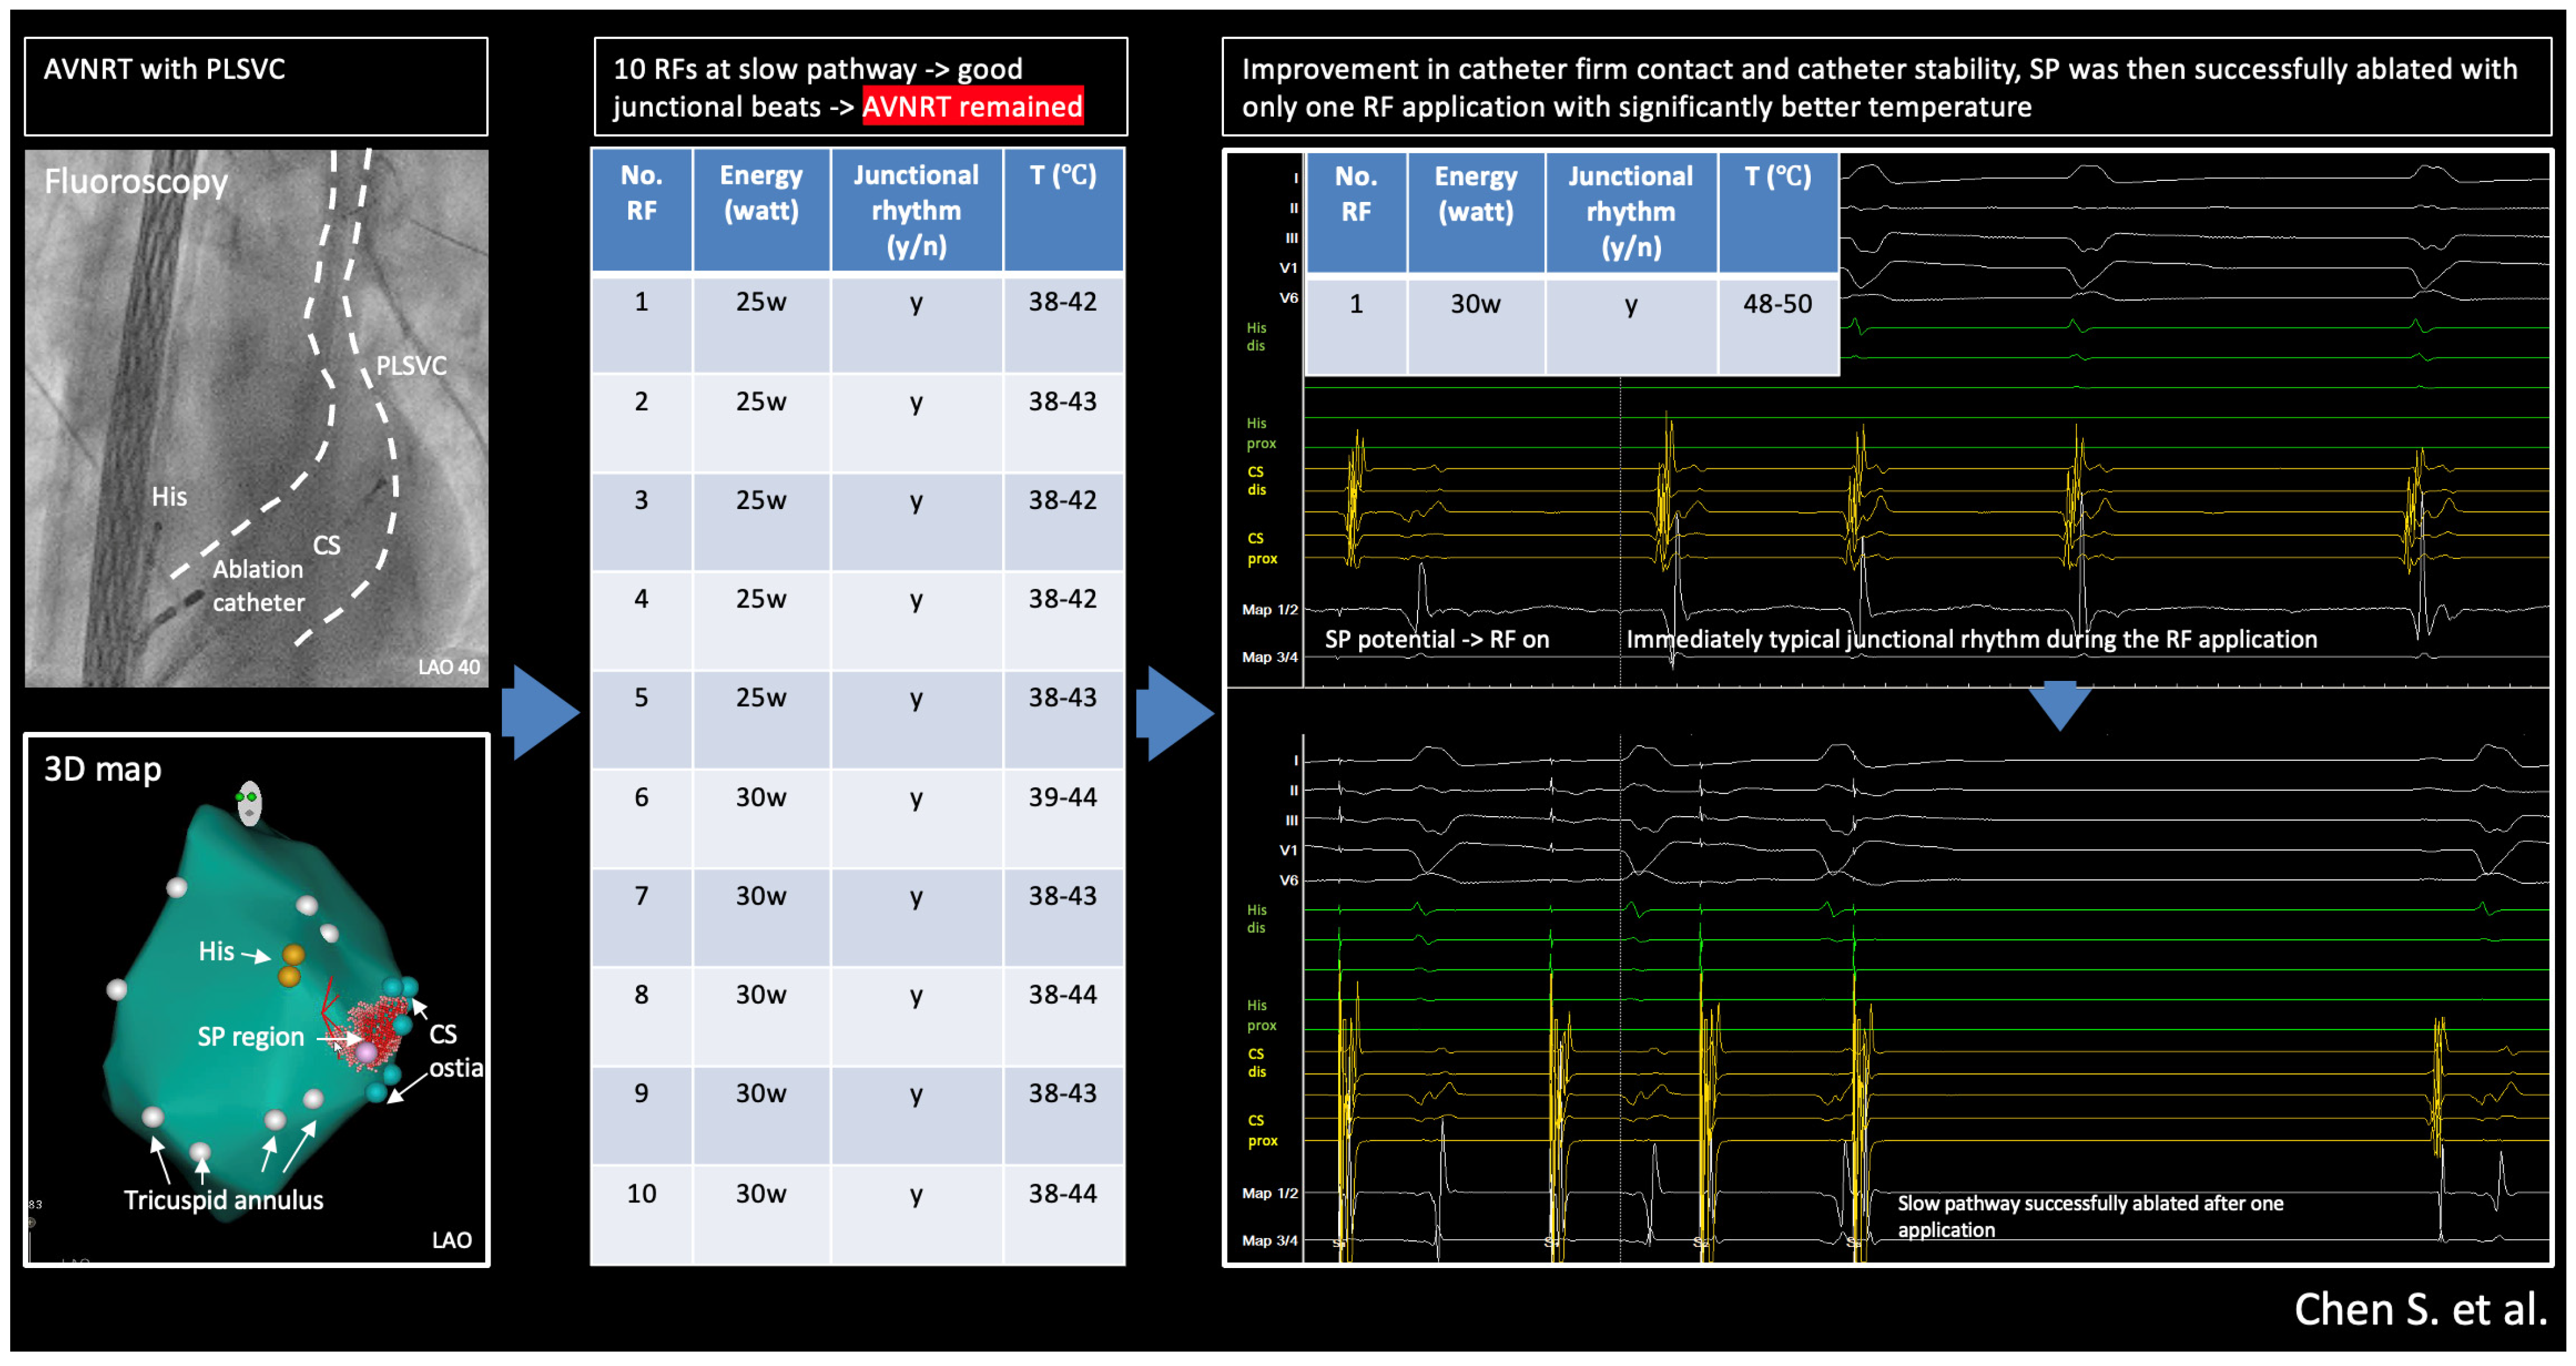

2. Method and Results

2.3. Ablation Strategy

2.4. Outcome